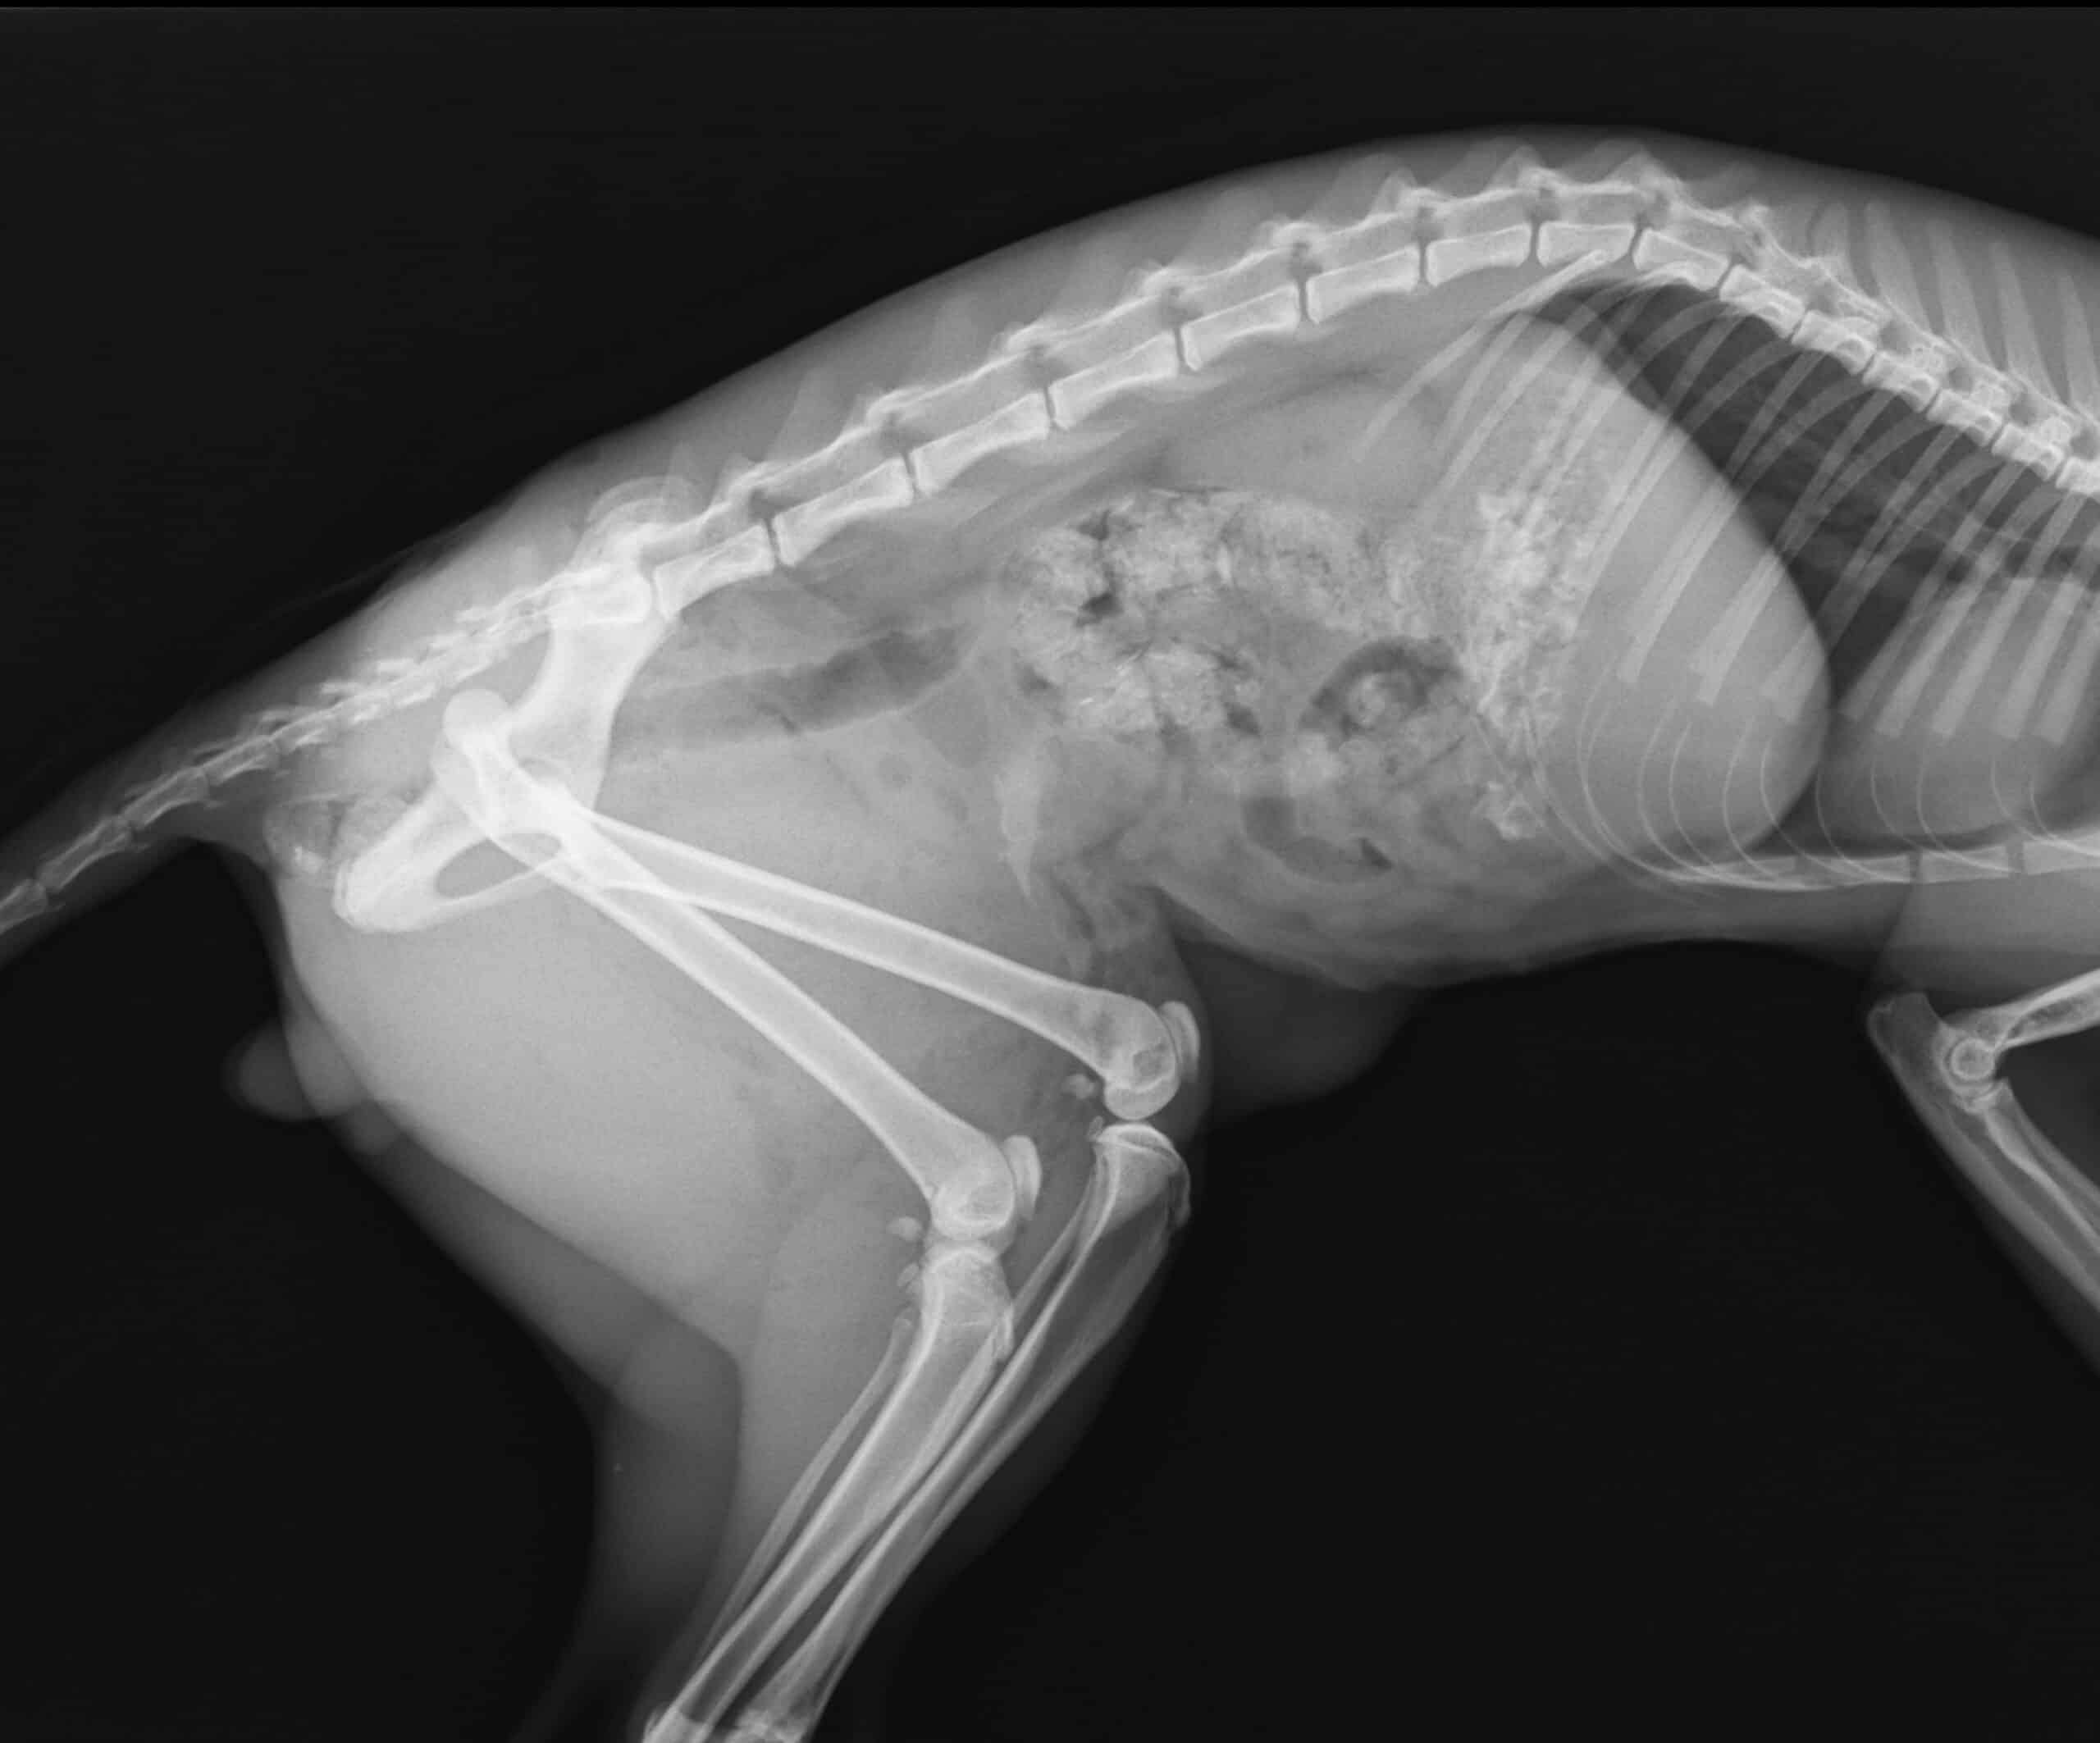

Digital radiographs (X-rays) provide high-resolution images of your pet’s bones and internal organs, enabling precise detection of fractures, arthritis, foreign objects, and other abnormalities. This advanced technology offers quicker processing times and superior image quality compared to traditional X-rays, allowing for faster and more accurate diagnosis and treatment planning.